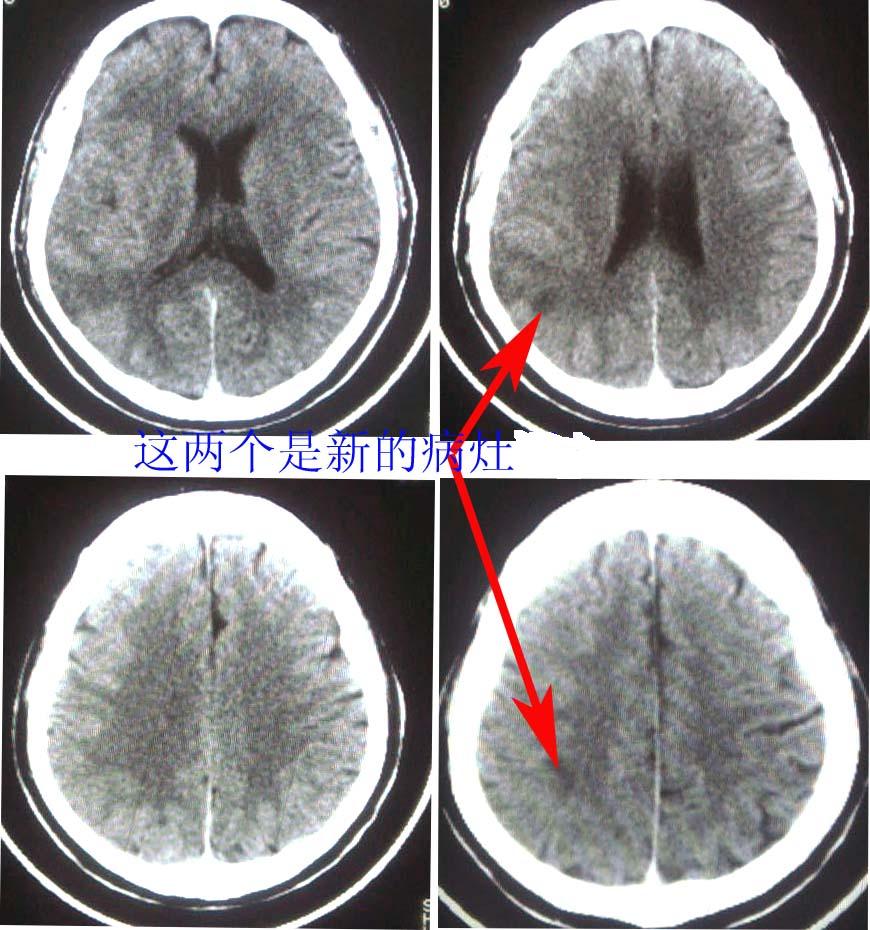

这是一个49岁 男性患者,近两天头痛,自感言语不利。既往有脑梗塞病使。麻烦各位老师看看有没有新的病灶。谢谢!

是新发病灶,另外左枕叶可见软化灶形成.

从密度考虑是新病灶

右侧颞叶的低密度应考虑是新发病灶。

支持,新病灶密度不是很低,境界不很清楚